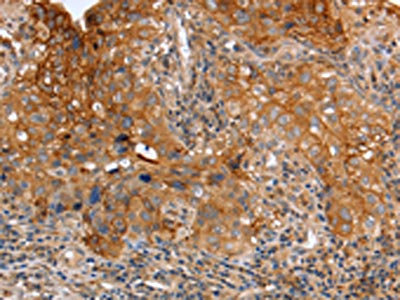

The image on the left is immunohistochemistry of paraffin-embedded Human lung cancer tissue using CSB-PA236241(PLAUR Antibody) at dilution 1/60, on the right is treated with fusion protein. (Original magnification: ×200)

The image on the left is immunohistochemistry of paraffin-embedded Human cervical cancer tissue using CSB-PA236241(PLAUR Antibody) at dilution 1/60, on the right is treated with fusion protein. (Original magnification: ×200)